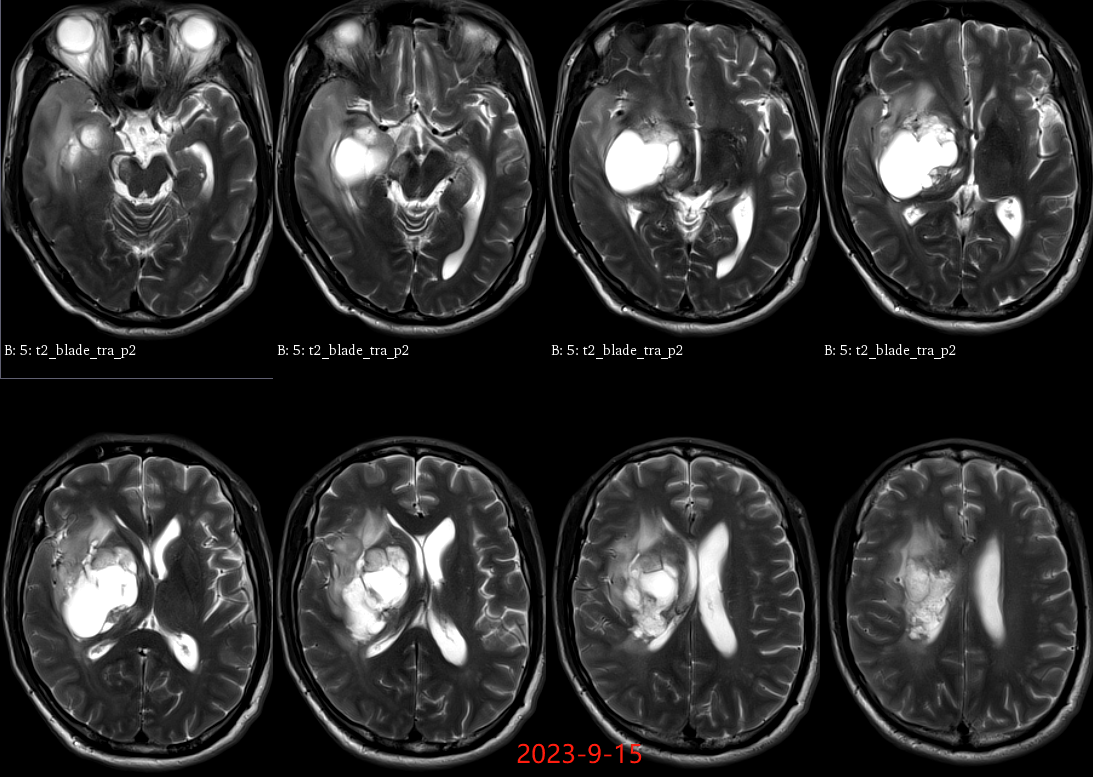

入院后于当地医院完善头颈部CTA检查未见明显血管发育异常,于2023-6-7行血肿钻孔引流术+脑室内颅内压监护探极置入术,引流一周后拔除引流管,期间未行尿激酶注射,患者反应情况逐渐好转,肌力未见明显改善。于出血后3周左右脑水肿基本消退后出院行康复治疗,治疗过程中患者肌力曾有所改善,左侧肢体肌力最好可达3级。术后3月左右患者一般状态逐渐变差,无发热,神志逐渐进展为昏睡状态,左侧肢体肌力1级,复查颅脑CT示水肿较前明显加重,颅脑MRI示右侧基底节区长T1长T2团块状病变,内有囊变,呈不均匀菜花样强化,考虑为高级别胶质瘤可能性大。遂行开颅病灶大部切除+去骨瓣减压术,术后病理提示高级别胶质瘤伴囊变,后续行同步放化疗STUPP方案,PTV:60Gy/30F/6周,替莫唑胺350mg化疗。患者右侧基底节区病灶相对稳定,2024-9-3复查颅脑MRI可见脑室内新发病灶。患者目前KPS 60分,神志清醒,精神差,反应迟钝,语言对答部分切题,右侧肢体自主活动,左侧肢体肌力2级。